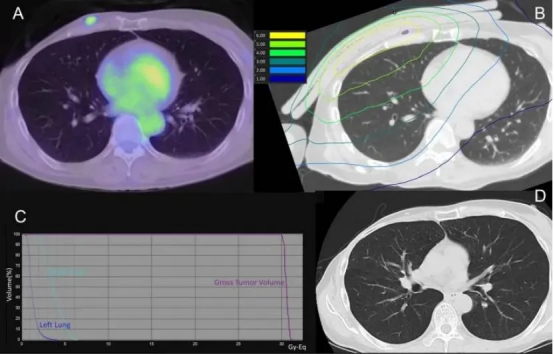

在日本江户川医院开展的一项临床研究中,一位72岁的乳腺癌胸壁复发患者接受了BNCT治疗。治疗前,PET-CT显示胸壁病灶代谢活跃;治疗6个月后,同一部位代谢显著降低,肿瘤明显缩小。

(A)硼中子俘获疗法(BNCT)肺部剂量分布图(紫色区域代表肿瘤大体靶区GTV);(B)治疗后90天的CT影像(未显示放射性肺炎迹象);(C)治疗前的弥散加权MRI影像;(D)治疗后90天的MRI影像(显示信号强度降低)

另一位61岁的患者,因多次复发、传统治疗手段用尽,在BNCT治疗后90天的随访中,CT显示肿瘤内部形成空洞,体积大幅缩小,且未出现放射性肺炎等副作用。

(A)硼中子俘获疗法(BNCT)肺部剂量分布图(紫色区域代表肿瘤大体靶区GTV);(B)治疗后90天的CT影像(未显示放射性肺炎迹象,且肿瘤大体靶区GTV缩小)